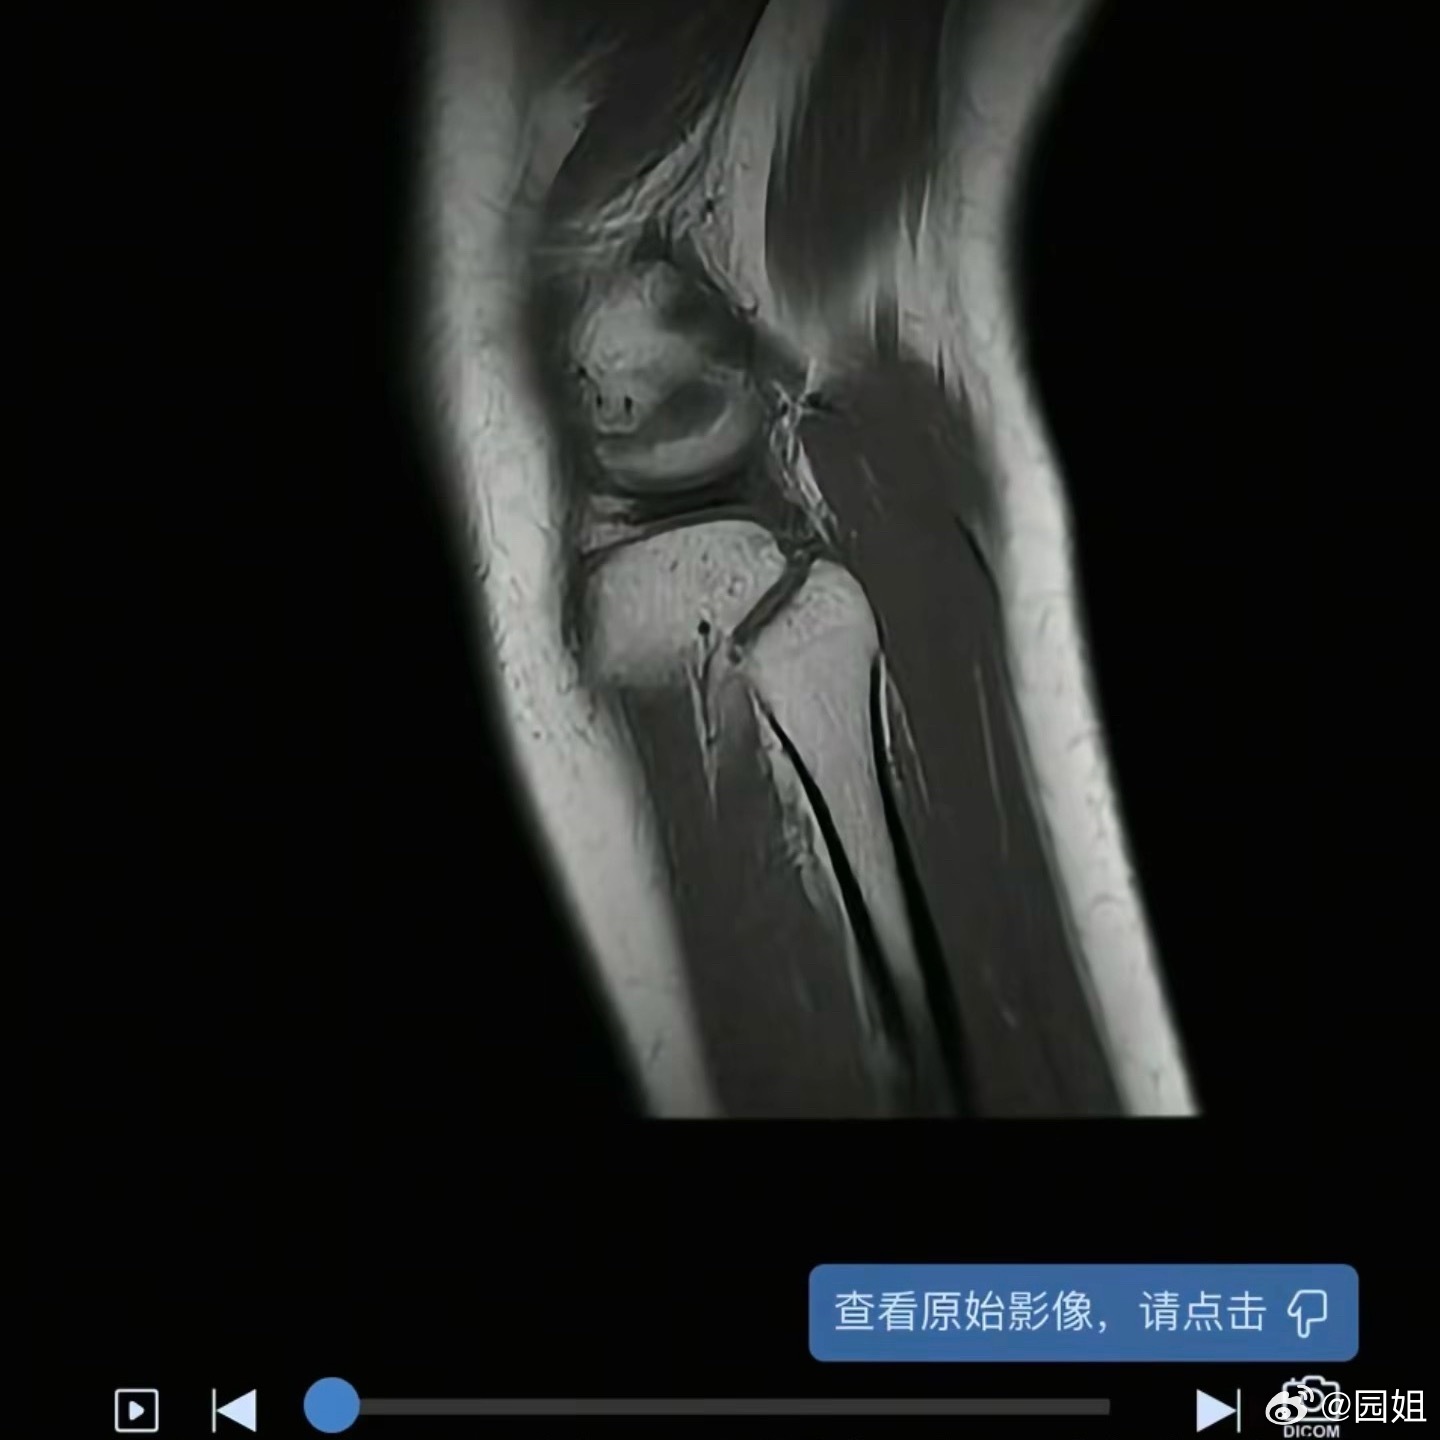

隔壁看到一个博主为了拍视频,把腿夹了,腿都夹坏了,太拼了,类似这种拍摄时候可得小

隔壁看到一个博主为了拍视频,把腿夹了,腿都夹坏了,太拼了,类似这种拍摄时候可得小心~